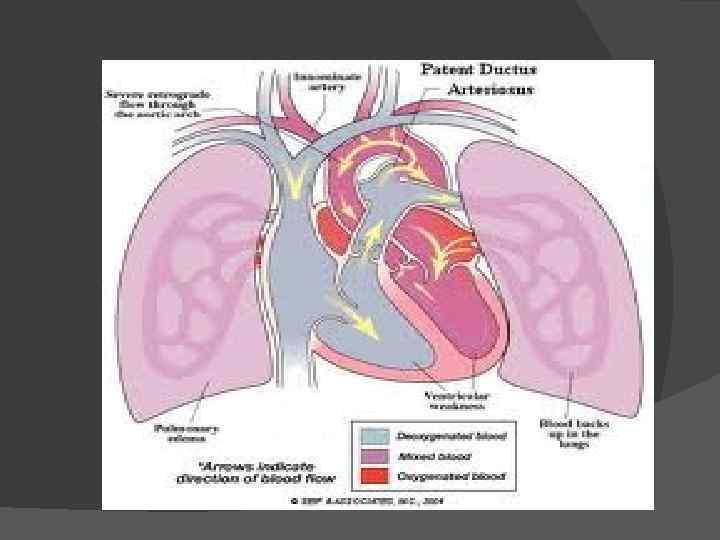

Первичное нарушение гемодинамики связано с разницей давления в аорте и легочной артерии. Через открытый артериальный проток кровь течет из аорты, где давление выше, в легочную артерию.

Следовательно, известная часть крови, выбрасываемая левым желудочком в аорту, переходит непосредственно в легочную артерию и через легкие, легочные вены и левое предсердие возвращается опять в левый желудочек

В результате правый желудочек компенсаторно гипертрофируется и расширяется. Расширяется и легочная артерия, которая наполняется кровью под большим давлением. Таким образом, артериальная кровь добавляется к венозной, следовательно, возникает сброс слева направо. Количество сбрасываемой крови различно в зависимости от соотношения диаметров протока и аорты.

Нередко большая часть крови, нагнетаемой левым желудочком в аорту, уходит в легочную артерию. В результате легочный кровоток преобладает над кровотоком большого круга. В связи с этим организм ребенка находится в состоянии хронического кислородного голодания, нарушается питание основных органов и тканей, в связи с чем может задерживаться физическое развитие и половое созревание.

Нарушения компенсаторных процессов. В редких случаях гипертрофические и склеротические процессы в легочных сосудах могут достигнуть такой степени, что давление в легочной артерии становится выше, чем в аорте. Сброс крови изменяет направление справа налево, т. е. венозная кровь начинает поступать в артериальное русло, появляется цианоз, и "белая" форма порока превращается в "синюю". Но при открытом артериальном протоке это встречается редко.